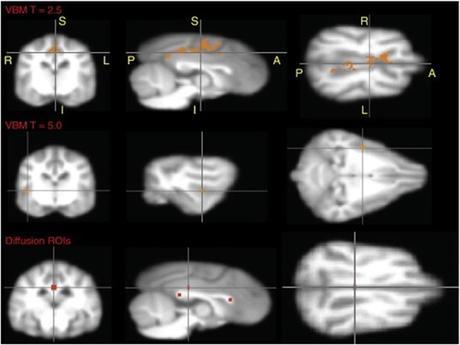

Les TOC sont considérés comme des troubles neurobiologiques. En d'autres termes, la recherche suggère que les cerveaux de personnes souffrant de TOC sont câblés de manière à générer leurs comportements particuliers. La recherche a impliqué trois régions du cerveau impliqués de manière variable dans le comportement social et la planification cognitive complexe, le mouvement volontaire, et les réponses de motivation et émotionnelles.

Mais il existe d'autres approches pour comprendre les TOC comme les approches génétiques et neurochimiques qui ont révélé quelques pistes sur les régions cérébrales impliquées, (à savoir le cortex, le striatum et le thalamus), et aussi la balance chimique à l'origine du trouble (probablement liée à une baisse notable de sérotonine, un neurotransmetteur crucial pour les sensations de bien-être).